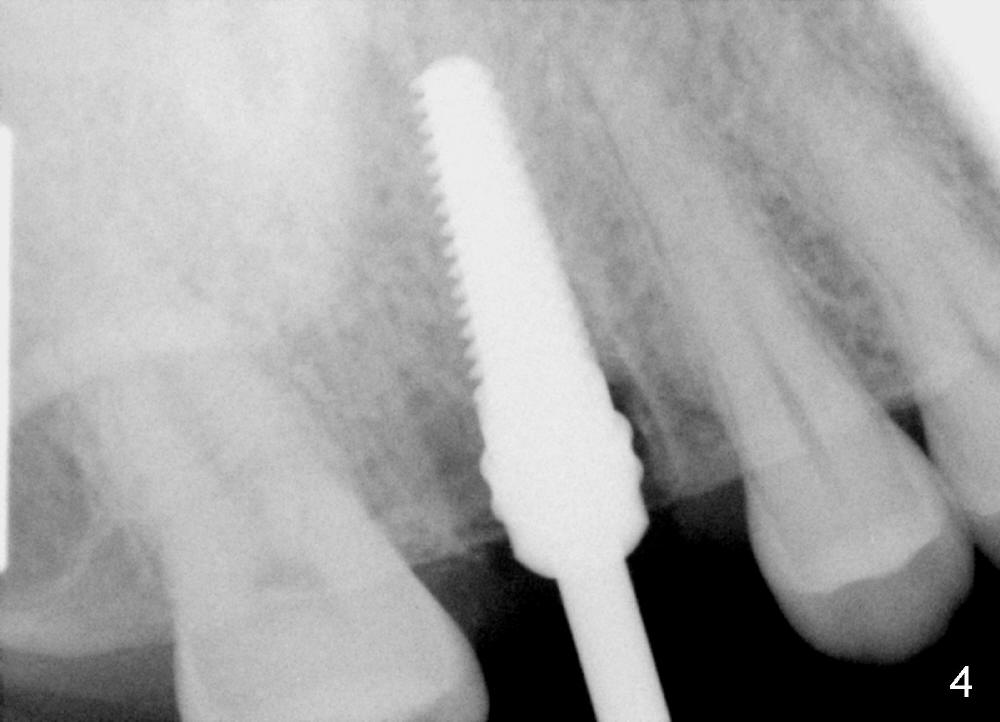

The tooth #3 has a crack line (Fig.1 ^). The septum (Fig.2 S) looks like an inverted pyramid (Fig.3), coronal part being pointed, whereas the apical broad. The shape of the septum is not so favorable to placement of tapered implant. Osteotomy starts with 1.5 mm pilot drill in the middle of the septum, followed by round tapered osteotomes 2 and 3 mm. The osteotomy begins to deviate into the mesiobuccal socket. The same osteotomes are used to re-direct the osteotomy palatally, followed by tapered drills, trying to move osteotomy palatally. A 4.5x17 mm tap is inserted with stability (Fig.4). Following using 5x17 mm tap at the depth of 12 mm, a 5.3x12 mm bone-level implant is placed ~ 1.5 mm below the crest, 1.5 mm above the septum (Fig.5). Demineralized cortical human allograft is placed in the remaining sockets and around the most coronal aspect of the implant (with a small piece of gauze placed in the implant well). After removal of the gauze, a piece of collagen membrane is pierced and carried by a 8.2x4/3 mm healing abutment and fixed in place (Fig.6 M). The periphery of the membrane is tucked underneath the gingiva. The wound is covered by perio dressing. The patient returns to clinic for follow up 8 days postop. There is no discomfort. In order to protect the collagen membrane (Fig.6), the perio dressing is intentionally not removed (Fig.7). Two weeks postop, the patient remains asymptomatic. After perio dressing removal, the membrane appears to have been resorbed (Fig.8 as compared to Fig.6). The bone graft (B), although exposed, remains in place and condensed, surrounded by healing healthy gingiva (*). The patient returns 2.5 months postop. The implant appears to osteointegrate (Fig.9, as compared to Fig.5). The buccal (Fig.10) and palatal (Fig.11) gingiva adapts to the healing abutment. When the healing abutment is removed for restoration 3 months postop, the gingiva looks healthy (Fig.12). A cemented abutment (5.8x4(2) mm) is placed; a crown is fabricated (Fig.13). The patient returns for recall 5 months post cementation. He reports food impaction distal to the crown. The gap mesial to the implant has closed (Fig.14).